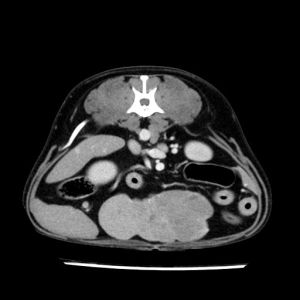

La lesione focale epatica , la ceus,la Tac e il chirurgo .